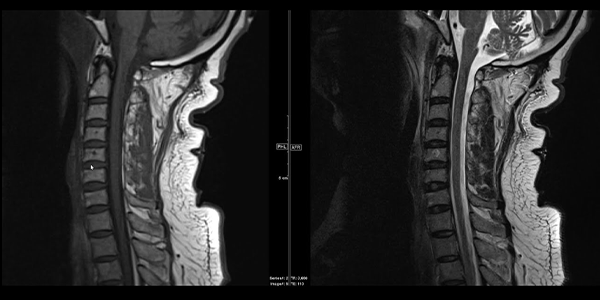

Kontrastsız MR, Manyetik Rezonans Görüntüleme (MR) teknolojisi kullanılarak vücudun iç yapılarının detaylı görüntülerini elde etmek için kullanılan bir yöntemdir. Bu yöntemde, damar yoluyla kontrast madde enjekte edilmez. Kontrastsız MR, beyin, omurilik, eklemler, iç organlar ve kaslar gibi birçok farklı bölgenin incelenmesinde kullanılabilir.

• Omurga MR: Omurga fıtığı, omurga darlığı ve omurilik tümörleri gibi omurga hastalıklarının teşhisinde kontrastsız omurga MR kullanılabilir.